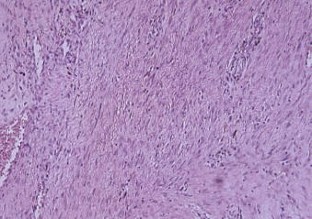

Fig. 1.